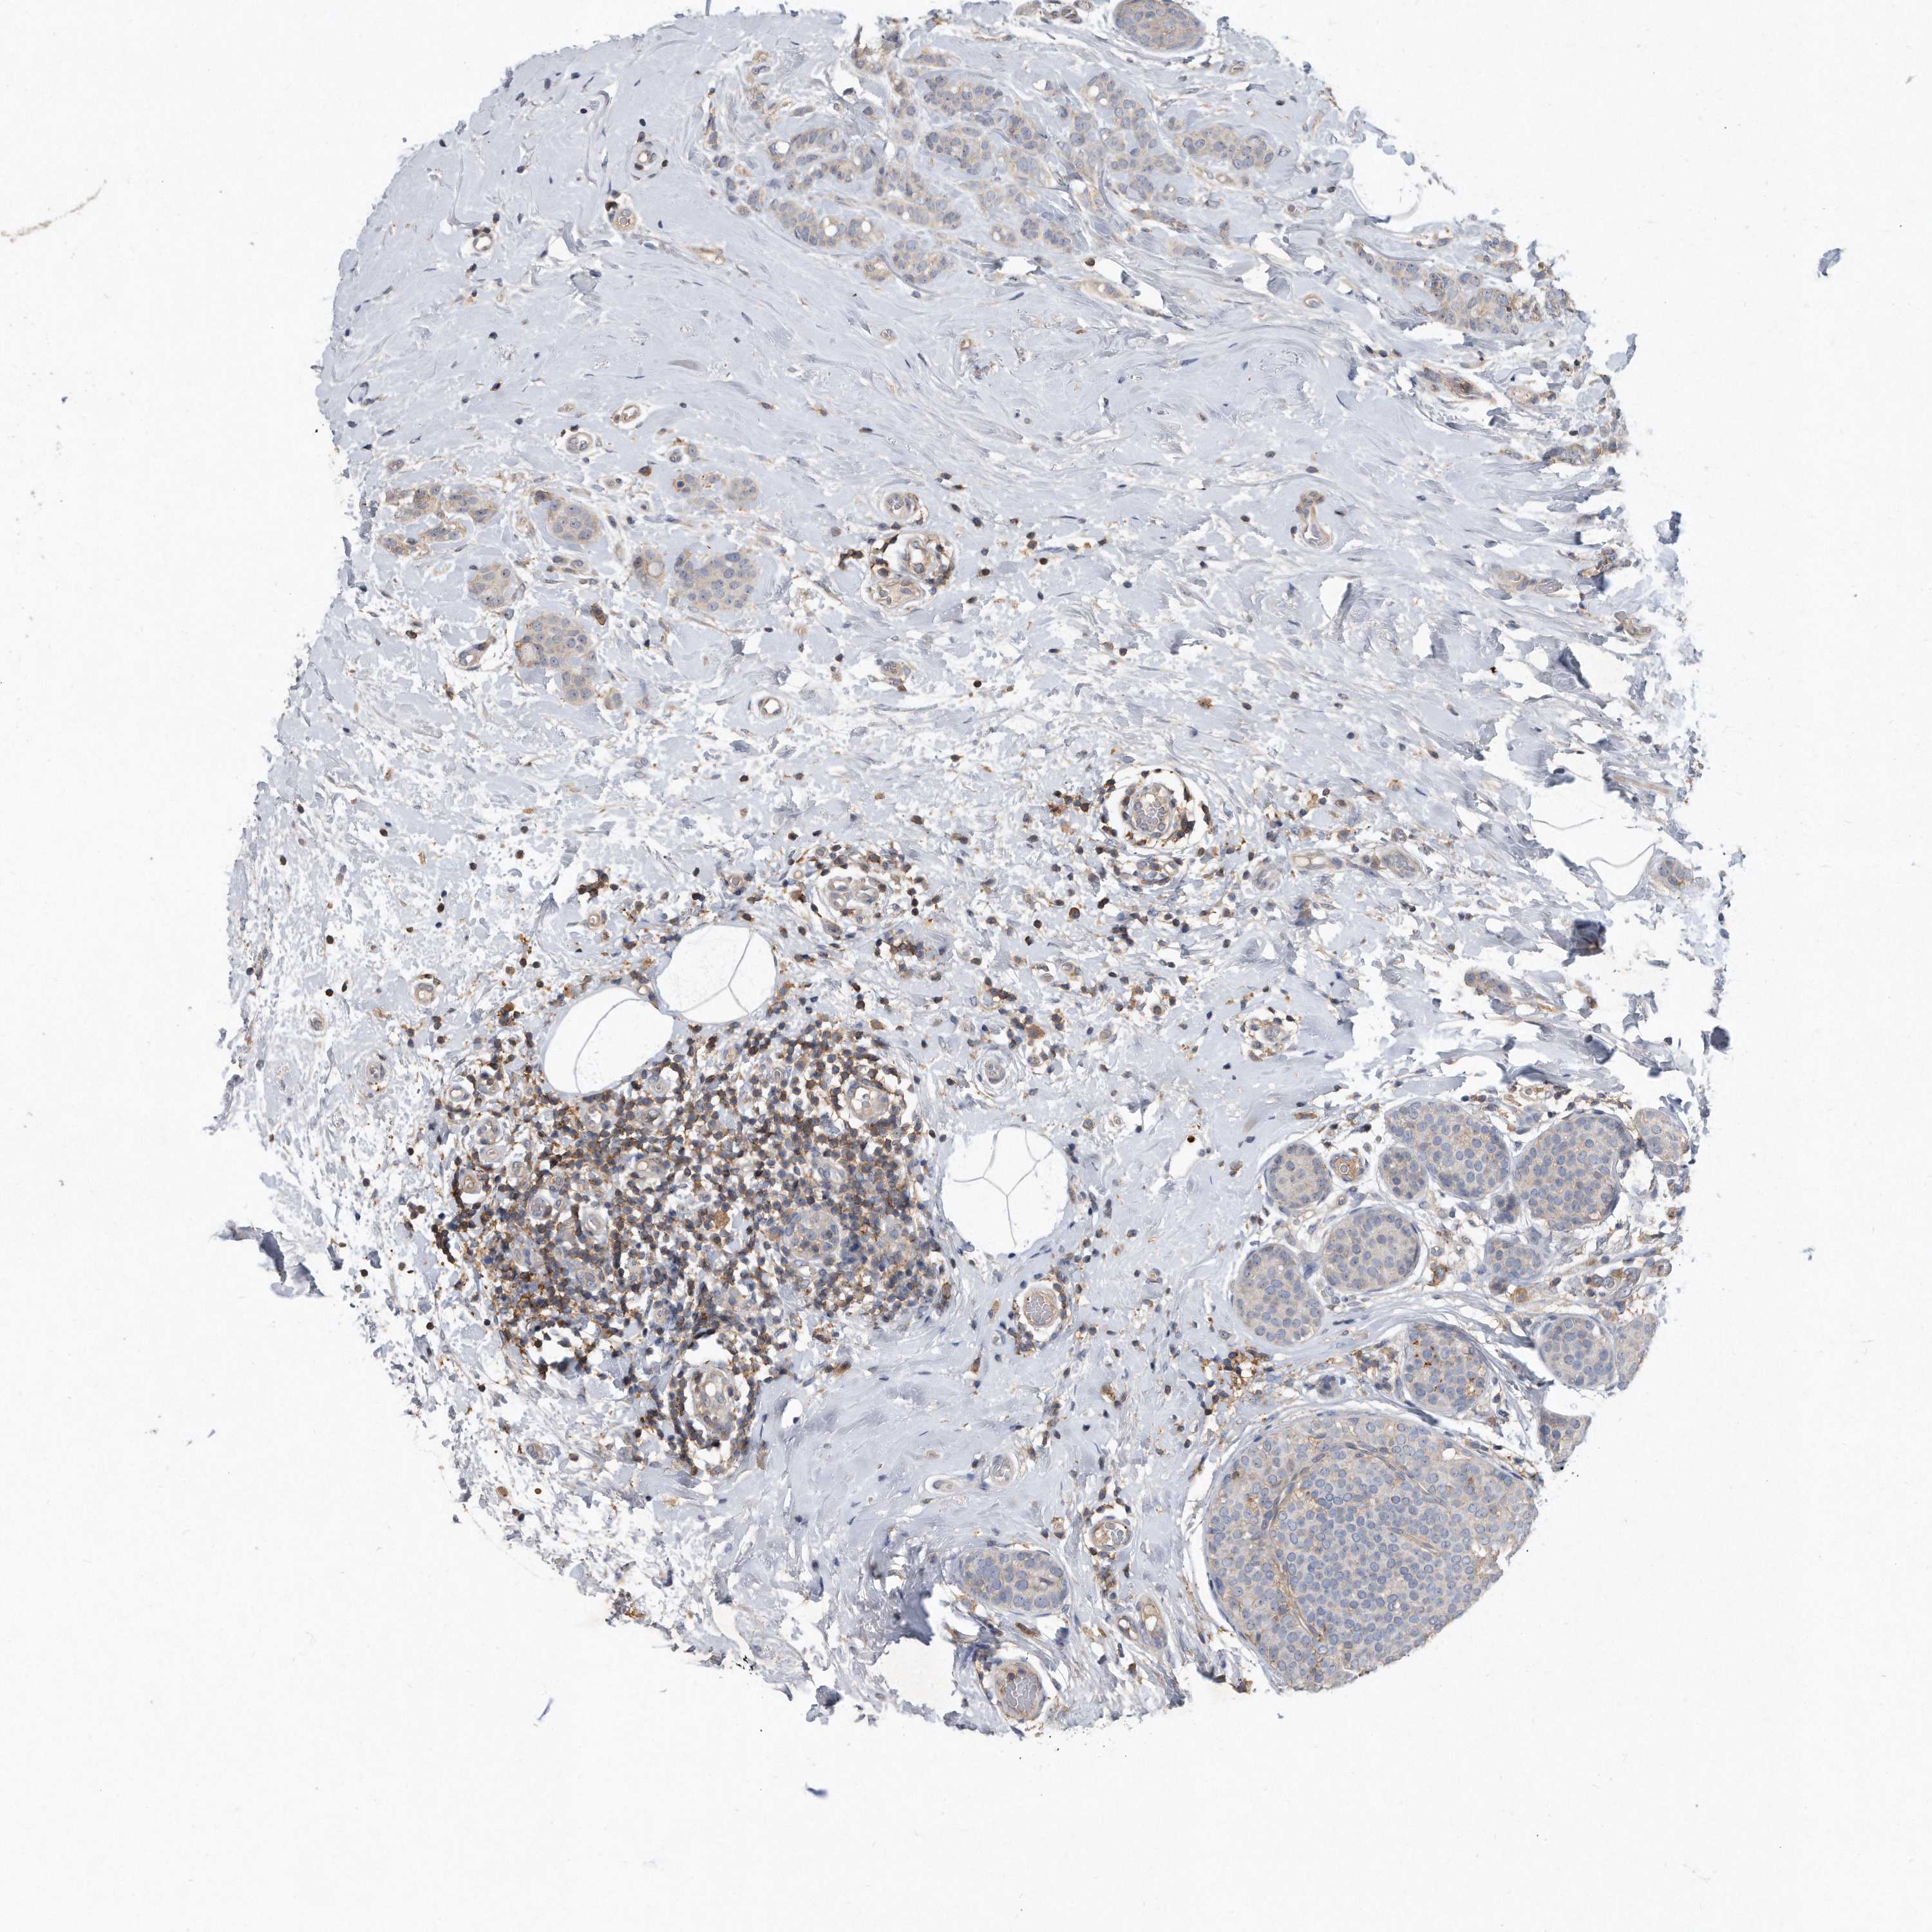

CANCER BREAST CANCER Show tissue menu

BRCA TCGA BRCA VALIDATION PROTEIN EXPRESSION